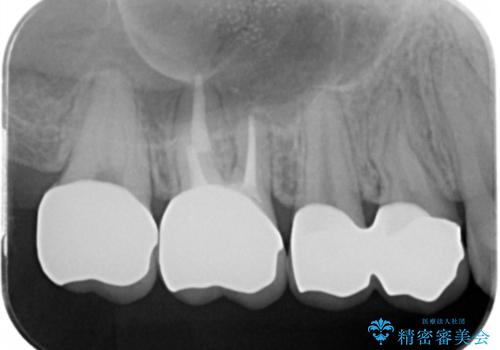

歯周外科を行い歯ぐきの整備を行うセラミック治療

銀歯周囲の虫歯再発や、歯ぐきよりも深い虫歯、根尖性歯周炎と言った複合的な問題を、

歯周外科、精密根管治療、セラミック治療を行い、妥協のないセラミック治療を計画します。

虫歯の再発可能性を限りなく低く抑えるためには、虫歯の徹底的な除去を行ったのちの精度の高いセラミック治療が必須です。

今回の治療では歯ぐきの問題を解決するため、歯周外科を行いました。